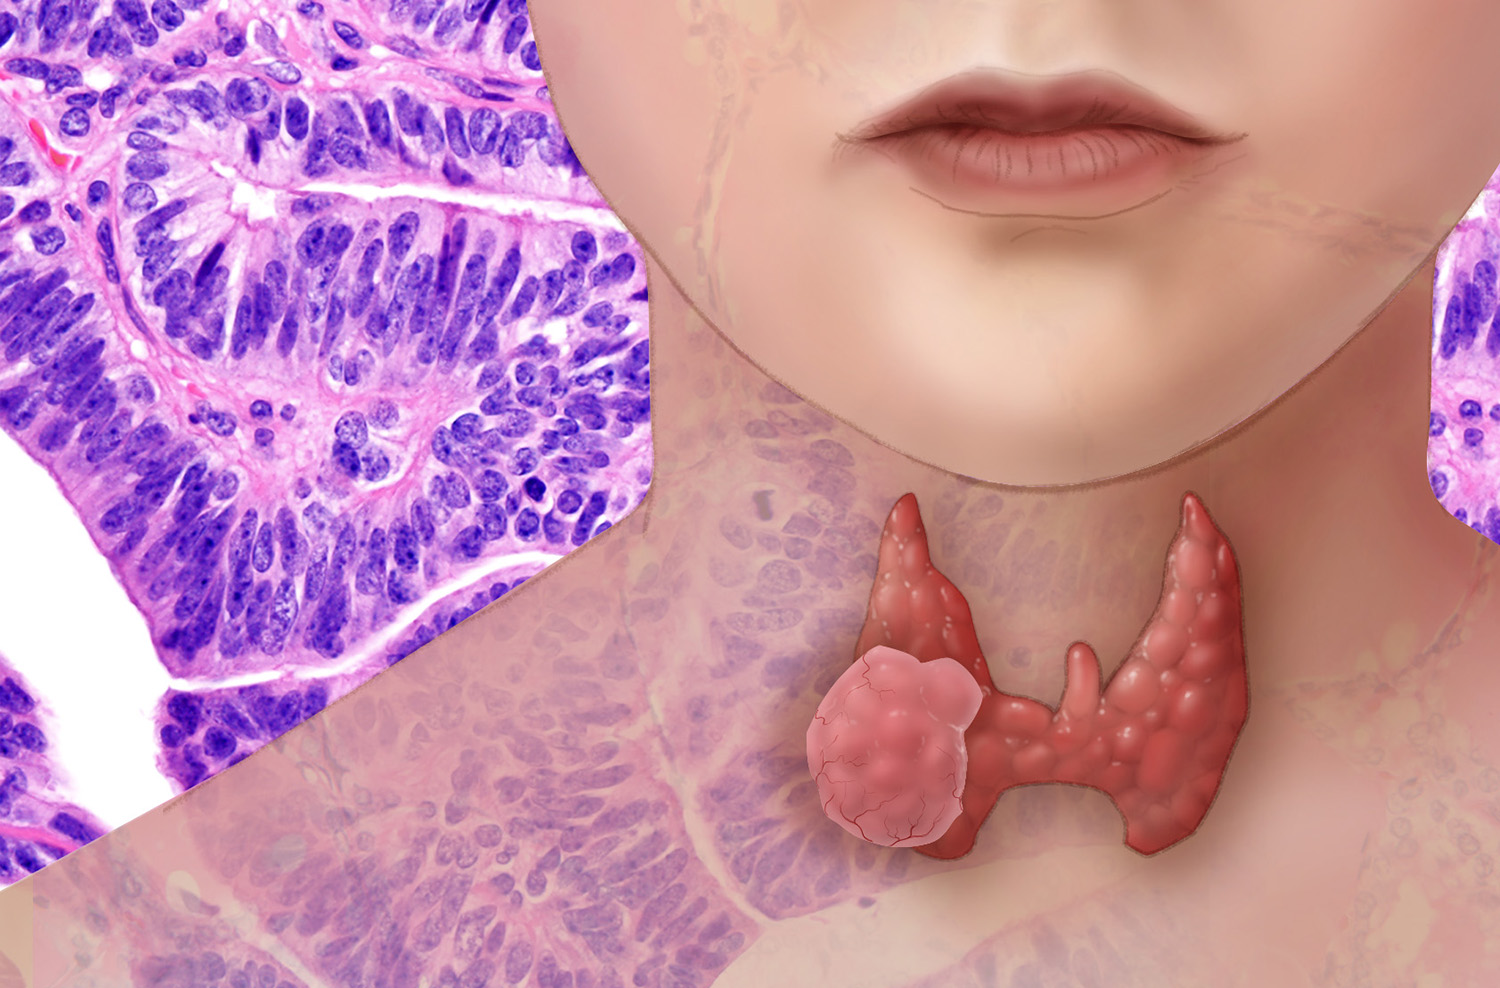

A recent report published by TheBusinessResearchCompany on Thyroid Cancer Drugs Market provides in-depth analysis of segments and sub-segments in the global as well as regional.

- The Thyroid Cancer Drugs Global Market Report 2020 which provides strategists, marketers and senior management with the critical information they need to assess the global thyroid cancer drugs market. The report covers the thyroid cancer drugs market’s segments- Ipilimumab, Cabozantinib-S-Malate, Caprelsa (Vandetanib), Doxorubicin Hydrochloride, Lenvatinib Mesylate, Nivolumab, Vandetanib, hospitals, oncology clinics, research organizations, radioiodine ablation, thyroid stimulating hormone (THS) suppression, chemotherapy, targeted multikinase therapy, and others.

- Combination drugs are increasingly being used in the treatment of thyroid cancer as they are more effective and help prevent cancer progression. A combination drug includes two or more active pharmaceutical ingredients (APIs) combined in a single dosage form. These drugs reduce the development of drug resistance and prevent the growth of cancer cells.